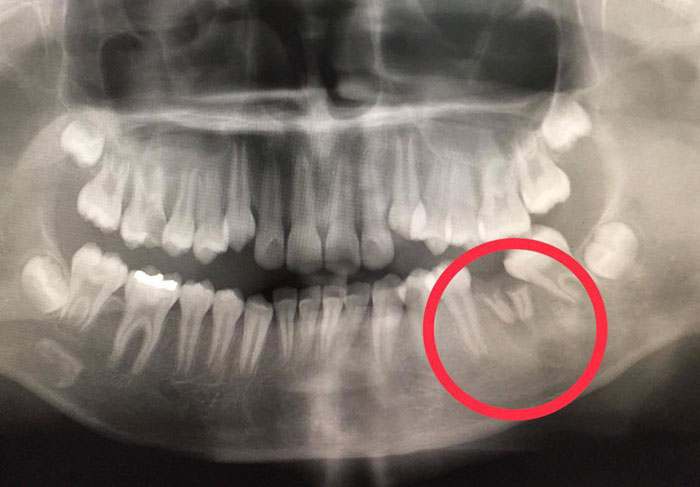

และแล้วก็พบสาเหตุของหนองเจ้ากรรมนั่นก็คือ....เมื่อเอ็กซเรย์ทั้งปาก

พบฟันกรามล่างซี่ที่ 36 ผุจนเหลือแต่ตอฝังอยู่ในเหงือก